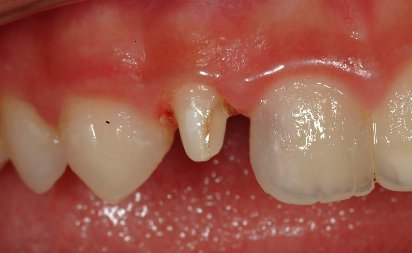

本次治療採一次約診完成根管治療,充填後如圖二 .

圖二 |